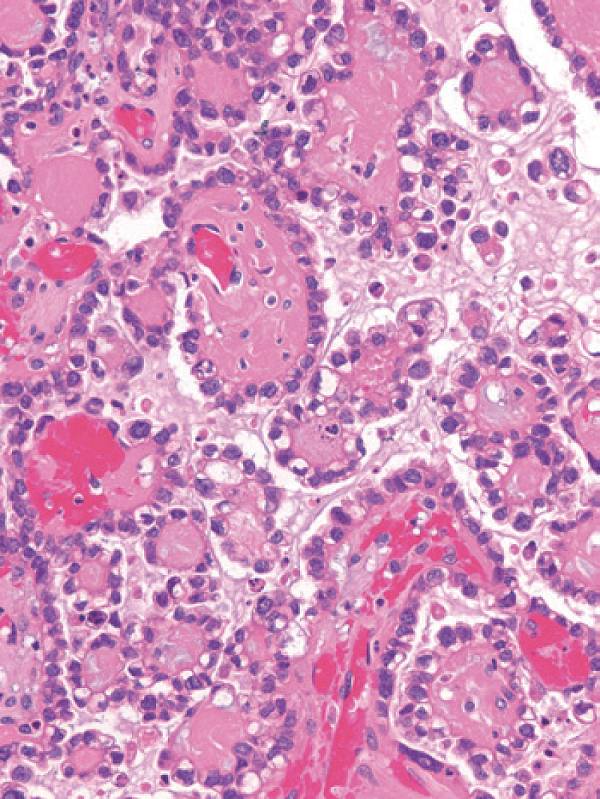

彩图4-2 卵巢透明细胞癌呈现典型管状囊性结构

彩图4-3 卵巢透明细胞癌

乳头状结构中基质玻璃样变是许多透明细胞癌乳头中的典型特征